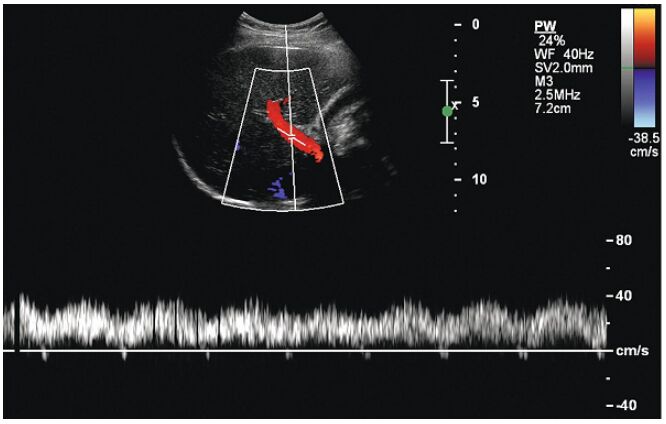

26.對於攝護腺切片(prostate biopsy),目前最常使用之定位影像工具為:(A)CT (B)MRI (C)transrectal ultrasound (D)fluoroscopy